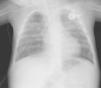

Se procede a la colocación de tubo pleural izquierdo, a las 48h presenta neumotórax derecho que precisa colocación de nuevo tubo pleural observándose fuga continua bilateral de aire. Ante la persistencia de neumotórax bilateral se realiza PSA izquierda y derecha los días 40 y 42 de ingreso, respectivamente. Se observa cese de la fuga de aire inmediata para hemitórax izquierdo, y a los 15min para el derecho. Las radiografías de control muestran resolución completa en ambos hemitórax (fig. 2). No presenta dolor ni otras complicaciones durante la PSA. Tras 2 años de seguimiento se encuentra asintomático.